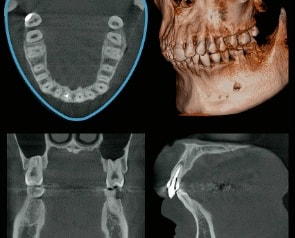

高精細なデジタルCTレントゲンを完備!

患者様に負担をかけず、状況を詳しく知ること!

デジタルCTパノラマレントゲンは今まで大学病院等に行かなければ撮影できなかったCT・パノラマ画像を院内にて撮影することができます。

デジタルX線センサーは超高感度で照射時間を短縮!

撮影範囲も設定可能で低線量にて高精細のレントゲン画像取得が可能となります。

子供さんにも優しいレントゲンです!

※フィルムを使用した撮影に比べ、人体に受ける放射線の量を、約1/4~1/10に抑える事が可能です。

また、従来行われていたレントゲン写真の現像などの手間もなくなり、画像も各ユニットモニターに表示され、ご一緒に見ることが可能!

それにより精細な状況説明や治療方針もお伝えできます。

デジタルCTレントゲン導入により環境にも優しく、スピーディーな対応が可能となりました。